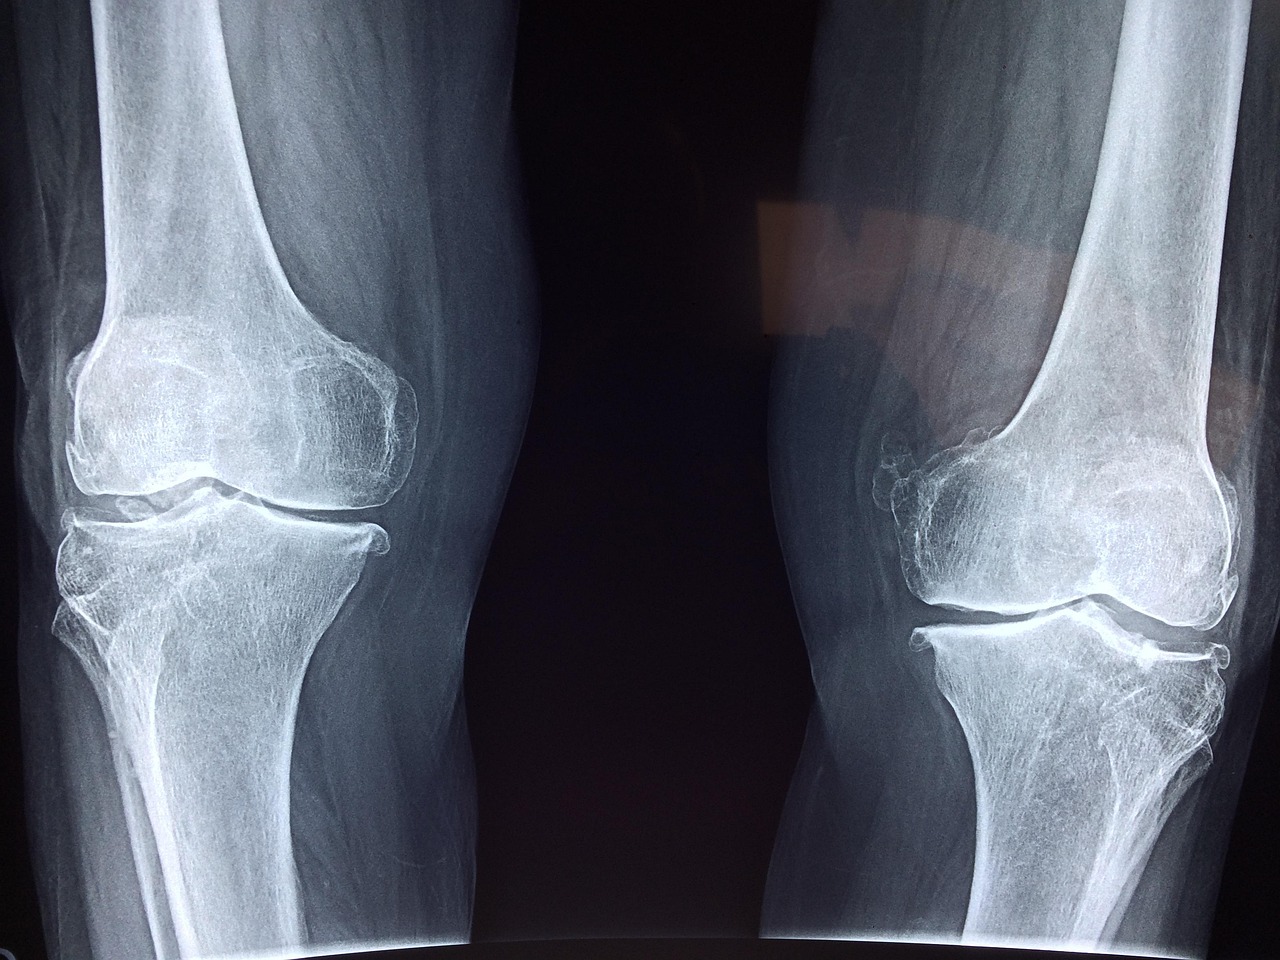

As our world becomes increasingly digital, more employees find themselves confined to their desks. While desk jobs often come with several advantages, prolonged sitting poses significant risks to our joint health. The joints, particularly in the lower body, experience reduced mobility and flexibility over time. This sedentary lifestyle can lead to stiffness, discomfort, and other joint-related issues. Regular movement is crucial to keep joint tissues hydrated and nourished. Furthermore, poor posture while sitting can exacerbate these problems, causing additional strain on the shoulder, back, and neck joints. Issues like arthritis can become more prominent when joints are not adequately utilized. It is essential, therefore, to devise strategies to mitigate these risks. Encouraging employees to stand or walk during calls, adopting ergonomic office furniture, and reminding them to stretch periodically can significantly improve their daily routine. Simple changes in behavior and work environment can lead to a more active lifestyle, thereby enhancing joint health over time. Ultimately, awareness of the impact of desk jobs on joints is the first step towards a healthier work culture that prioritizes well-being.

Prolonged sitting has been linked to various health complications beyond joint issues, potentially leading to serious medical conditions. In addition to affecting joint flexibility, it can also contribute to weight gain, cardiovascular diseases, and even diabetes. During sitting, our muscles tend to be inactive, slowing down metabolism and leading to a higher likelihood of obesity. The decreased blood flow to the joints resulting from long periods of sitting can cause inflammation, increasing the risk of conditions such as bursitis and tendinitis. Employees often report discomfort or pain in their hips, knees, and lower back from sedentary behavior, which can diminish their productivity and hinder overall job satisfaction. Introduction of standing desks, adjusted chair heights, and designated walking breaks within office hours can drastically improve workplace ergonomics and, consequently, joint health. Companies should prioritize strategies to minimize these risks by fostering an environment that encourages movement. Team challenges, walking meetings, and lunchtime yoga can serve as engaging solutions to promote joint-friendly habits during the workday. An emphasis on wellness can subsequently boost morale, enhancing both physical and mental well-being in the workplace.